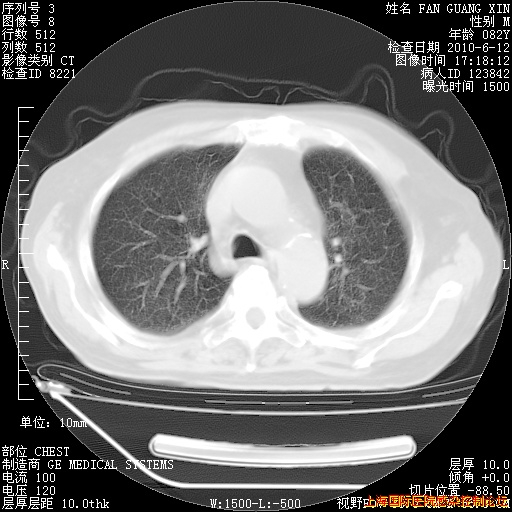

6月12日纵膈窗